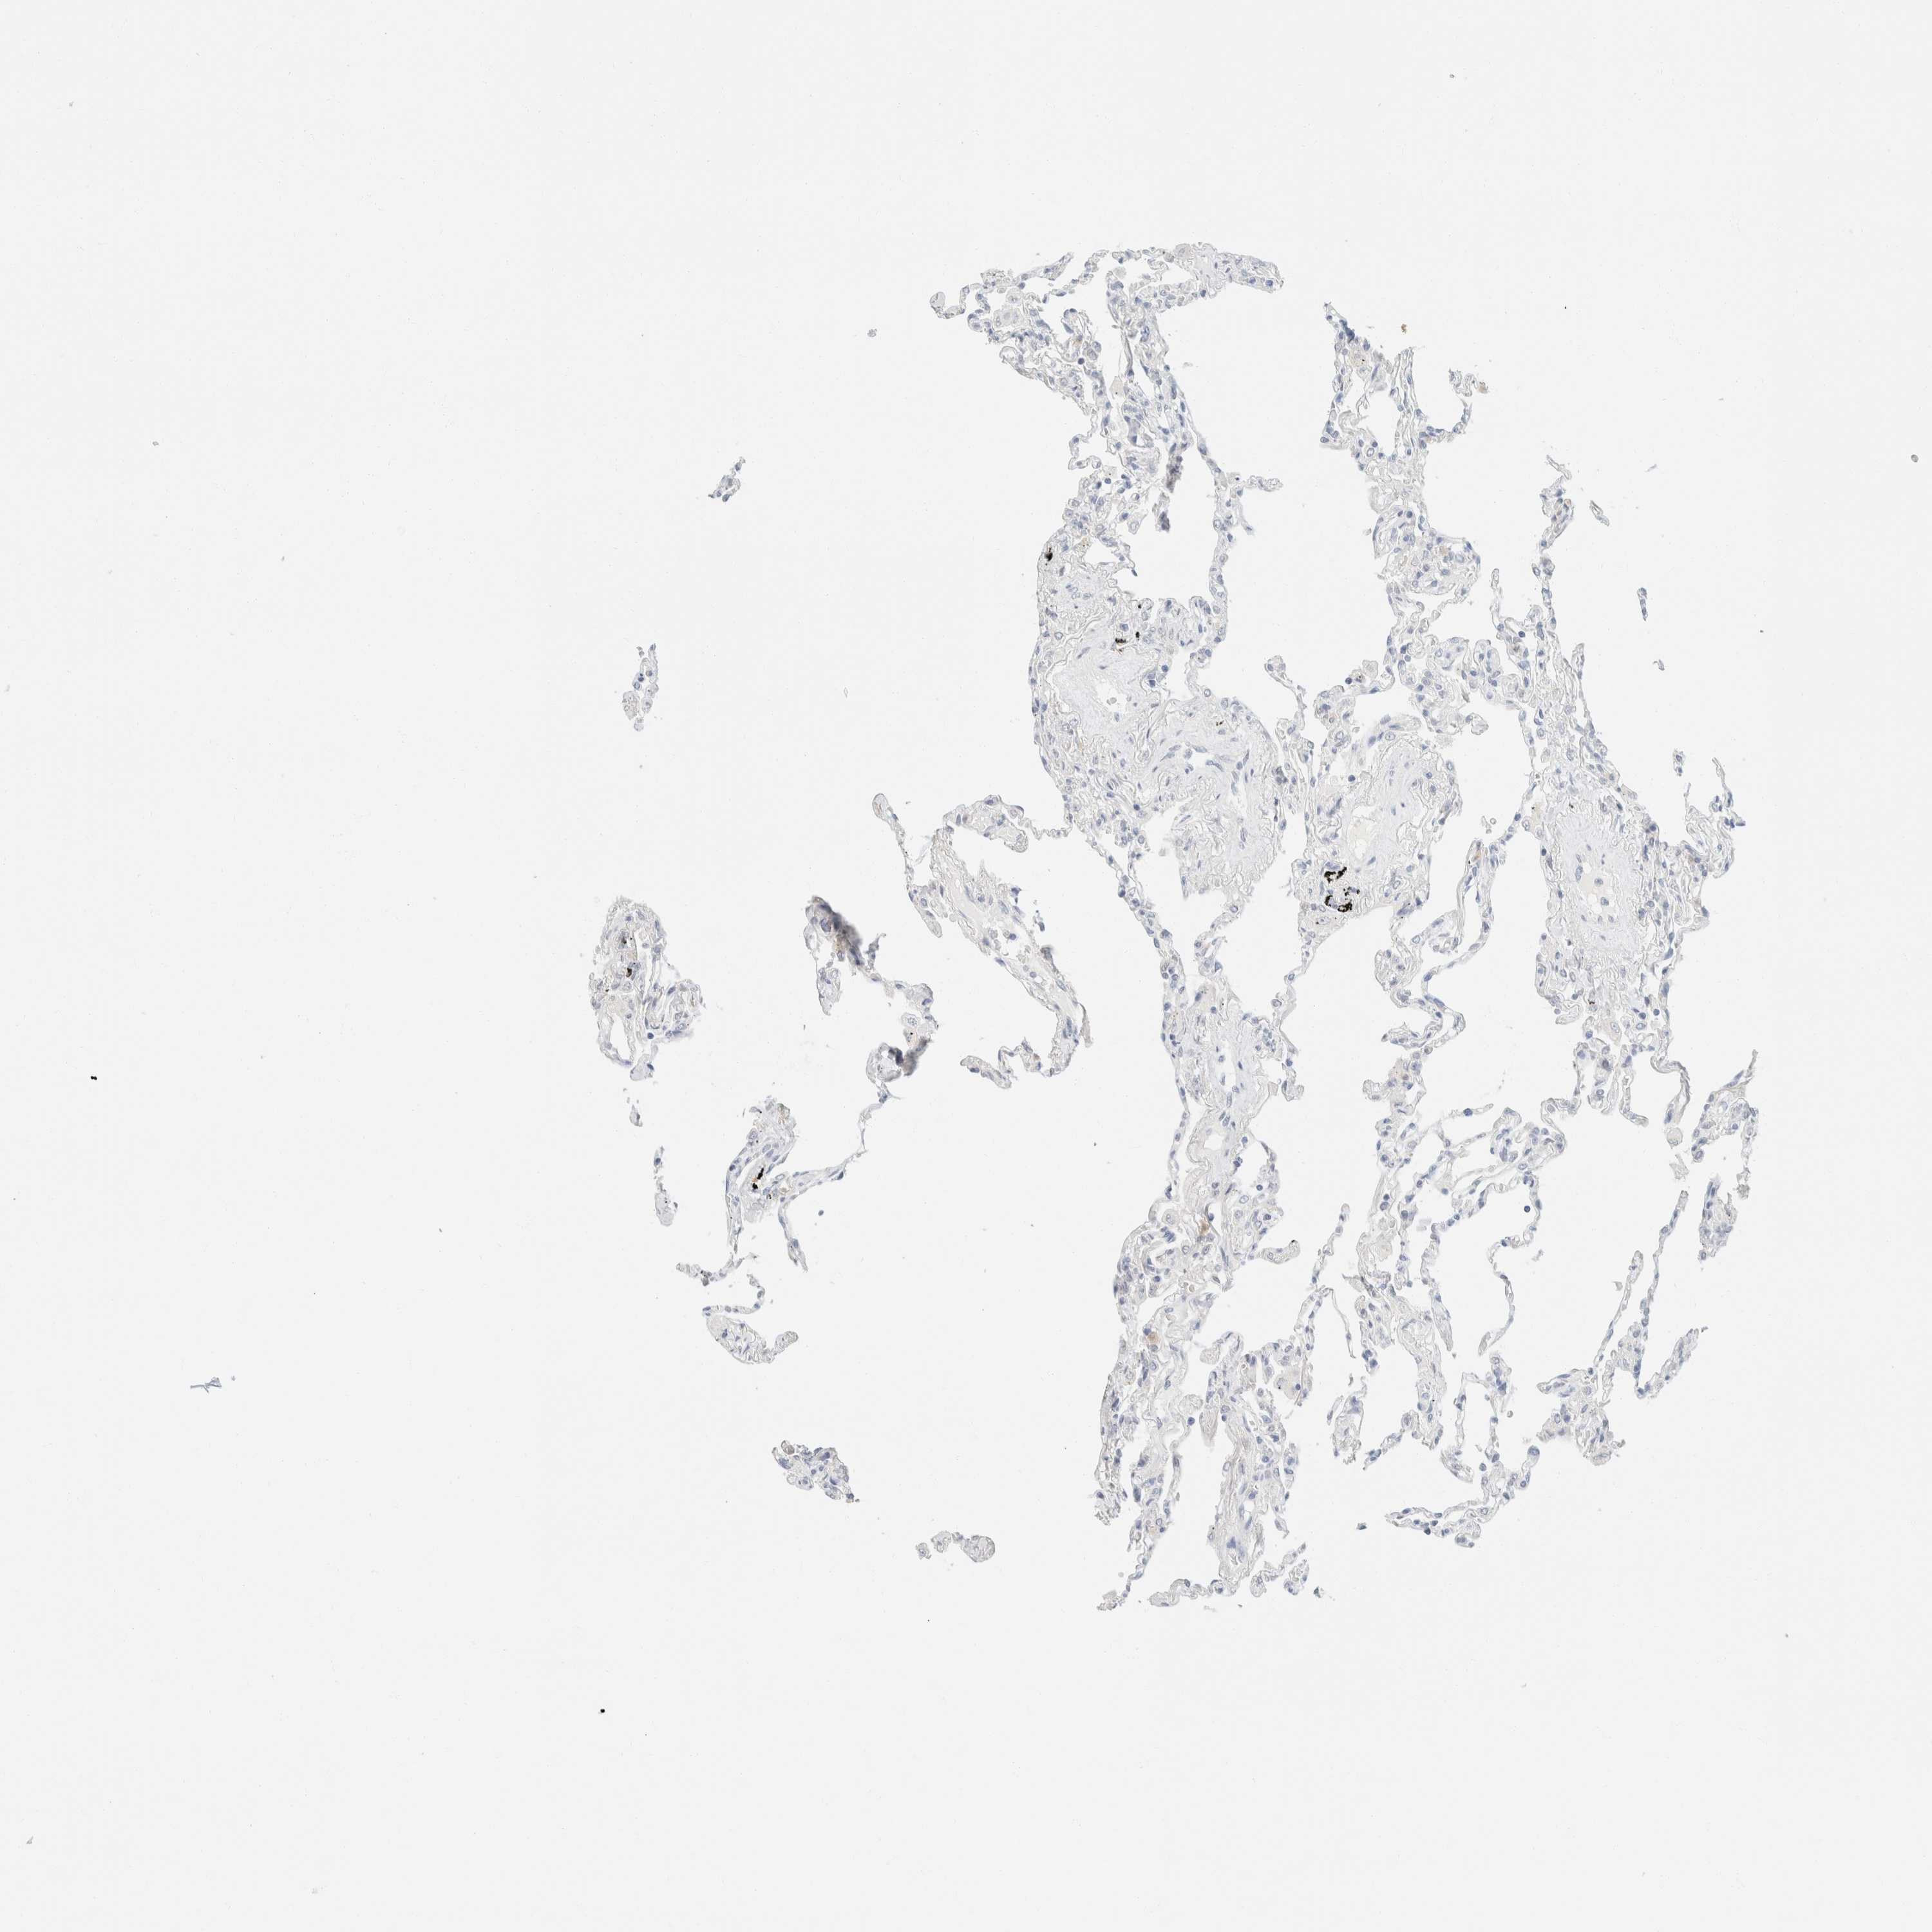

LUNG - Antibody stainingi

Antibody staining in the annotated cell types in the current human tissue is reported as not detected, low, medium, or high, based on conventional immunohistochemistry profiling in selected tissues. This score is based on the combination of the staining intensity and fraction of stained cells.

Each image is clickable and will lead to virtual microscopy that enables deeper exploration of all samples and also displays staining intensity scores, fraction scores and subcellular localization as well as patient and tissue information for each sample.

Antibody HPA024309Antibody HPA024684Antibody HPA027236Antibody CAB000032

Alveolar cells Not detectedNot detectedNot detectedNot detected

Macrophages Not detectedNot detectedNot detectedNot detected